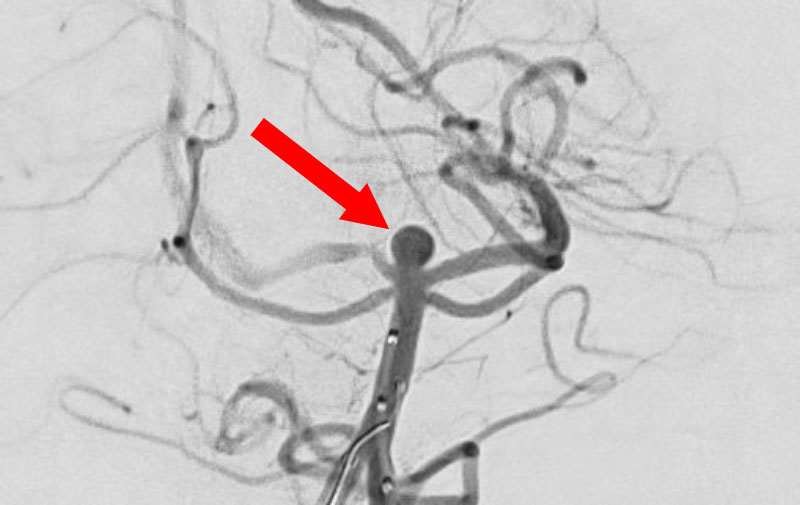

No.1631 手術前